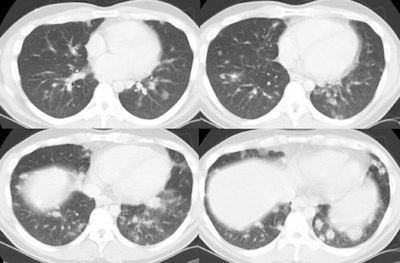

The patient below presented with complaints of cough, malaise, and a low-grade fever. The chest radiograph revealed some patchy left lower lobe airspace disease and vague nodular shadows- particularly in the lower lung zones. A chest CT was performed and demonstrated multiple nodular airspace abnormalities with variable margins. The lesions did not improve despite antibiotic therapy and all cultures were negative. Click images to enlarge.

Open lung biopsy confirmed the diagnosis of BOOP. Following institution of therapy with steroids the lung lesions resolved. Click images to enlarge.